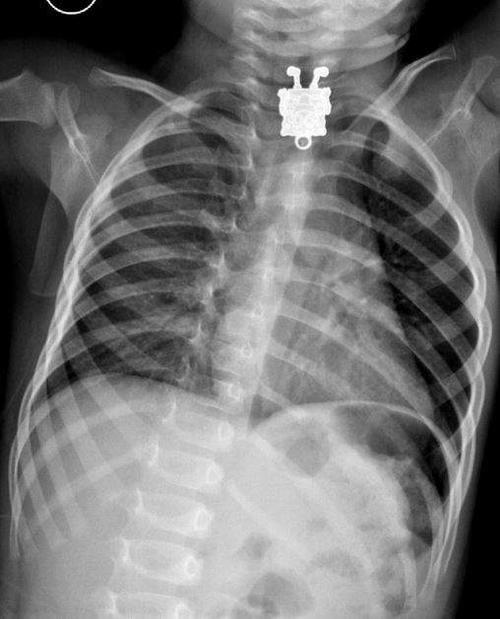

En este sitio se pueden encontrar ejemplos de niños que se tragaron objetos, como un anillo, un par de baterías o incluso un muñeco de Bob Esponja.